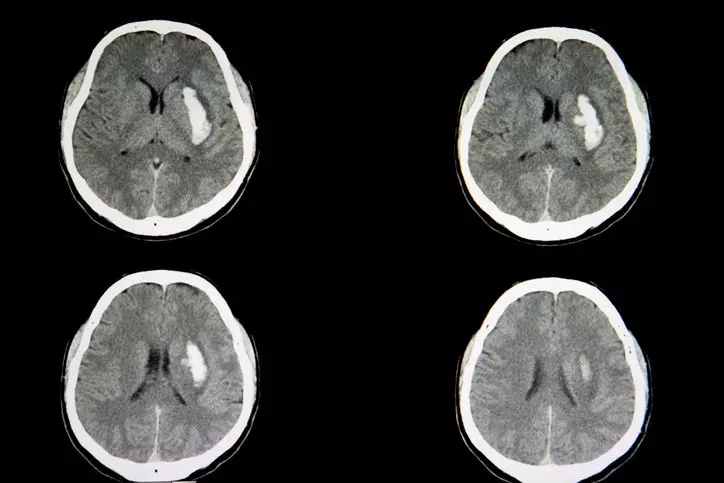

_Exames de imagem ajudam a diagnosticar a hemorragia intracriana e a extensão da lesão no cérebro. _Crédito,Getty Images

Como o próprio nome sugere, a hemorragia intracraniana é marcada por um sangramento que ocorre na parte de dentro do crânio.

“Trata-se de um sangramento dentro da caixa craniana, o osso da cabeça”, resume a neurologista Sheila Martins, professora da Faculdade de Medicina da Universidade Federal do Rio Grande do Sul (UFRGS).

Isso pode se desenrolar em algumas das estruturas que estão abaixo dos ossos da cabeça, como o cérebro ou as camadas que revestem as estruturas do sistema nervoso — conhecidas como meninges.

Segundo eles, a hemorragia pode ser epidural (entre o crânio e a dura mater, uma das membranas protetoras do sistema nervoso), subdural (abaixo da dura mater), subaracnoide (abaixo da membrana aracnoide) e intraparenquimal (nas próprias estruturas do cérebro).

O caso de Lula foi uma hemorragia subdural.

“O sangramento estava entre o cérebro e a meninge, embaixo de uma membrana chamada dura mater”, detalhou o neurocirurgião Marcos Stavale, que esteve envolvido com o procedimento.

“Esse sangramento comprimia o cérebro e foi removido. O presidente está com as funções neurológicas preservadas”, complementou o especialista.

Nesse caso, o acúmulo de sangue acontece na superfície do cérebro, no espaço que existe entre o órgão e aquelas camadas que protegem o sistema nervoso.